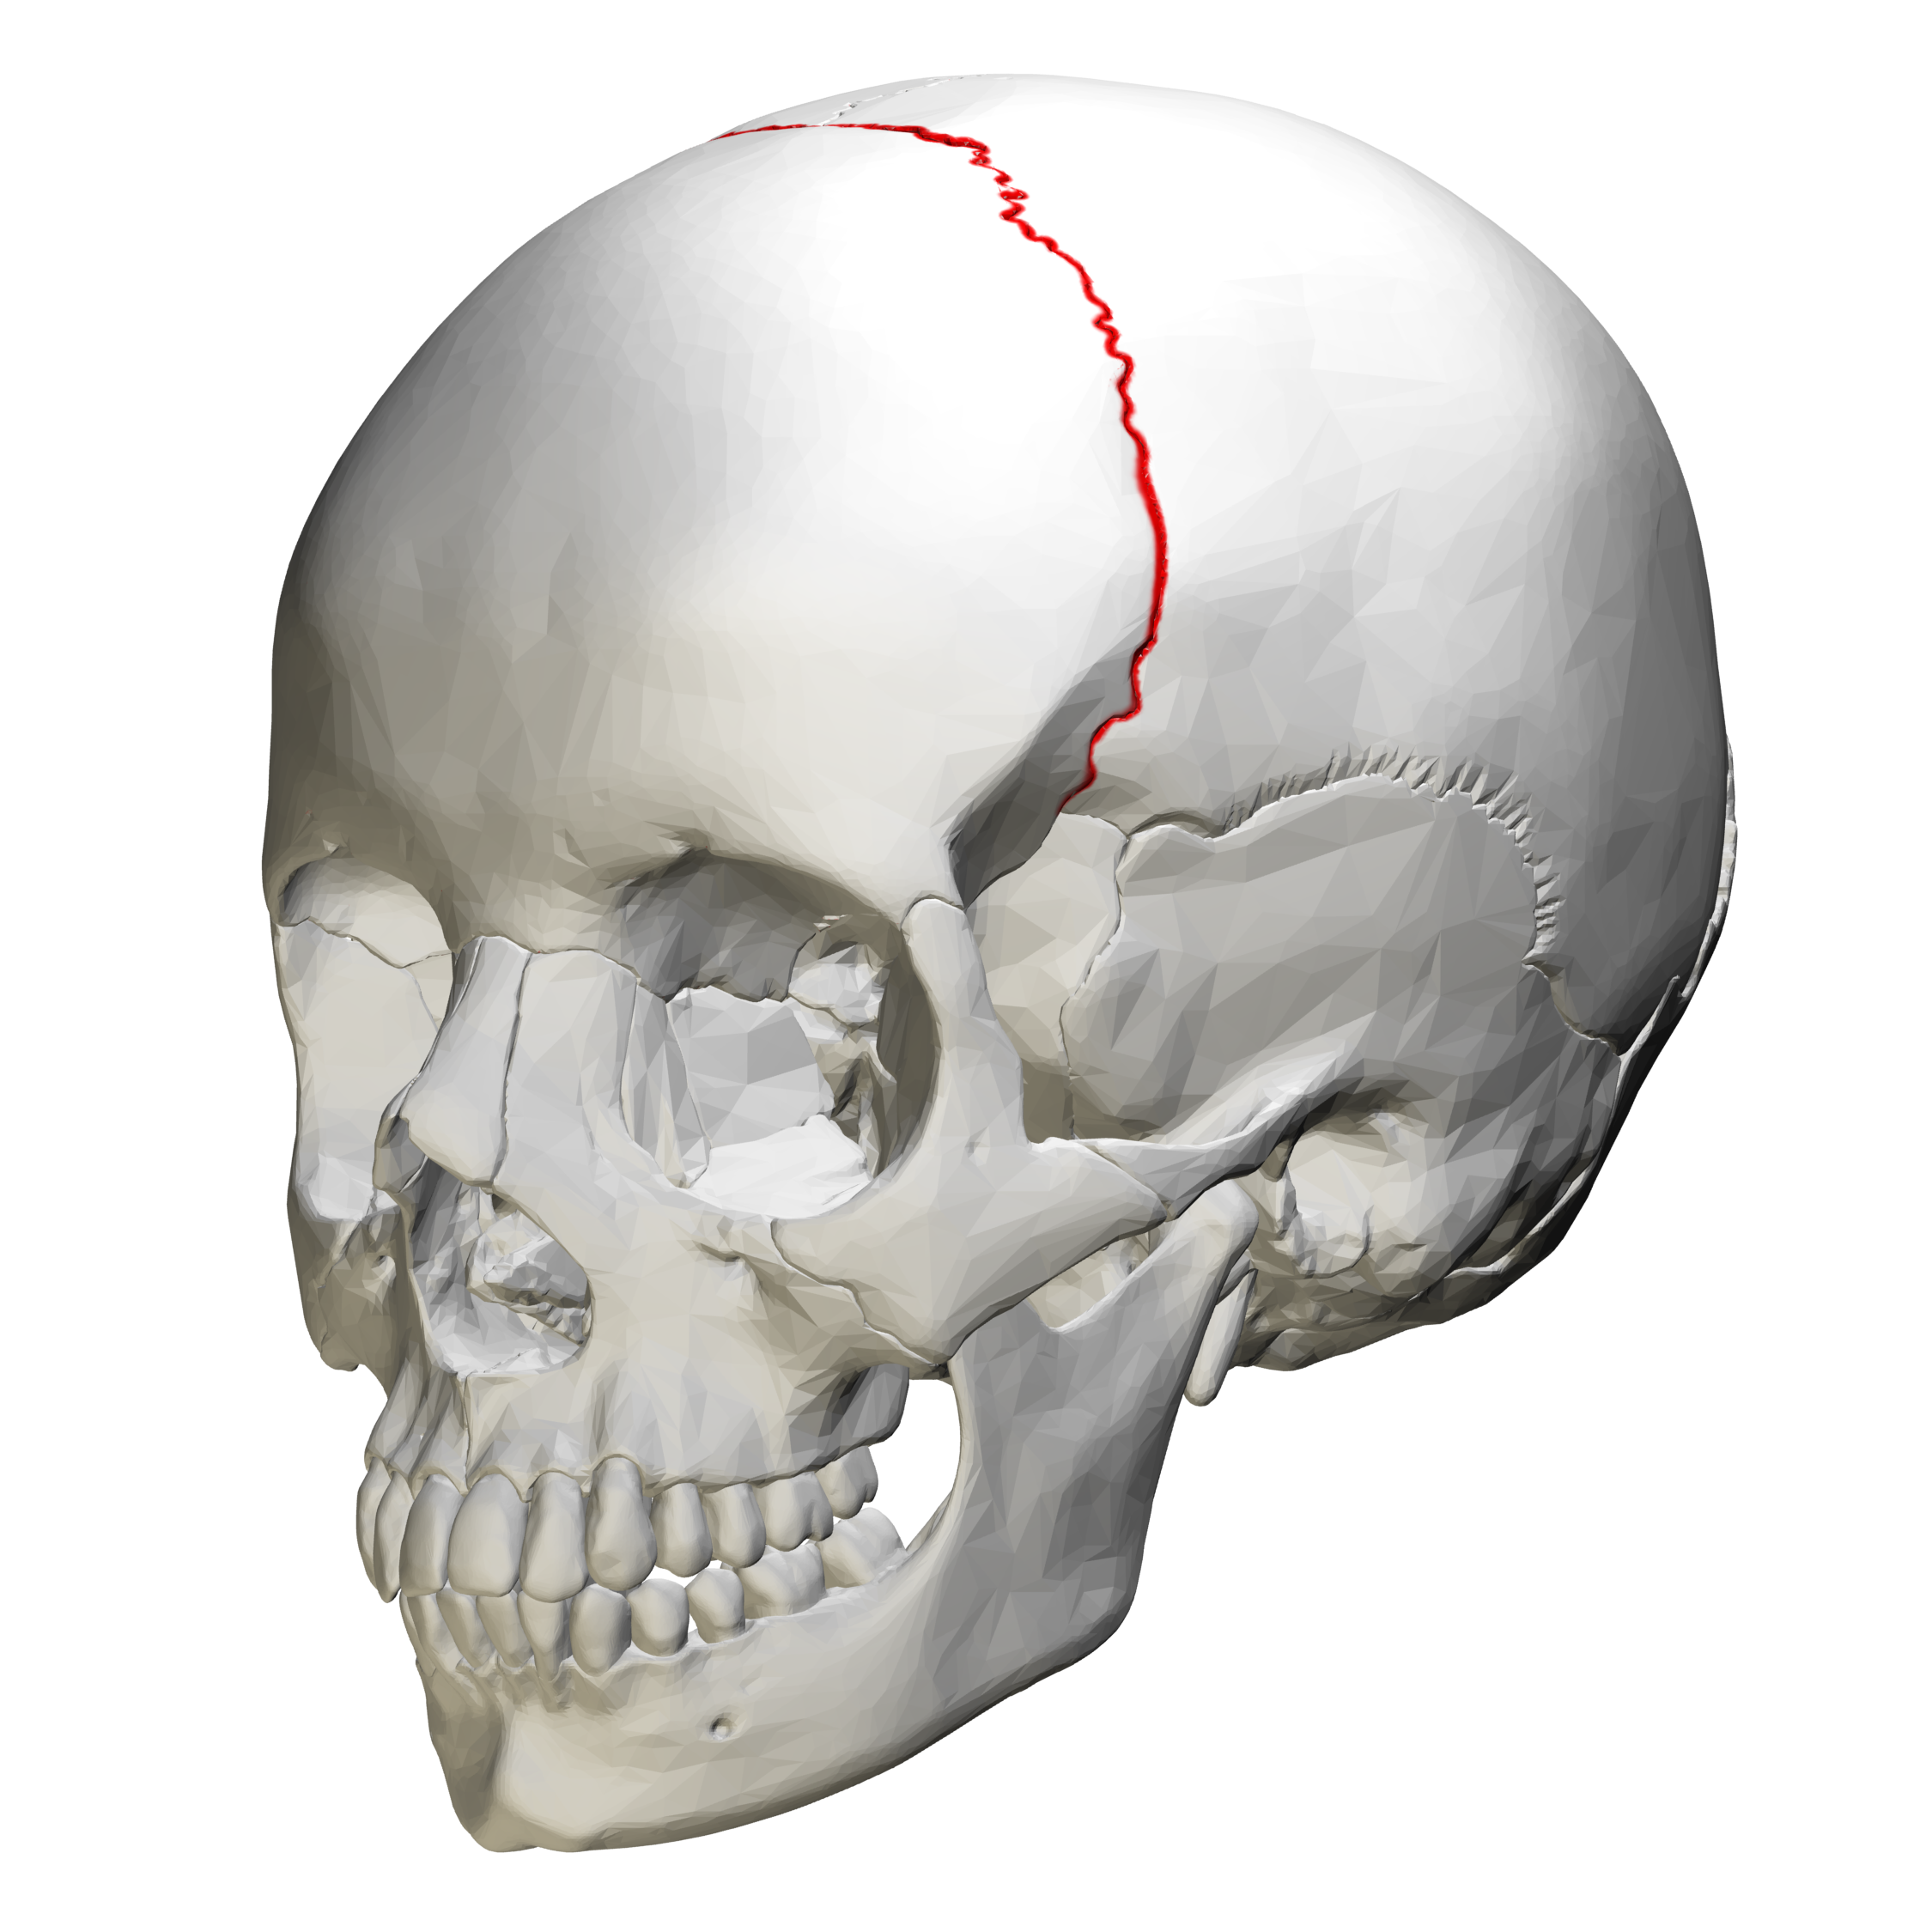

Man with long cranial base turned into short cranial base:

Short cranial base is so shit

Your maxilla has to stretch forwards as far as it can to try and catch up to the lower jaw, and even then it fails to keep up, falls behind, and you get an underbite. Just because you were born with an abnormally short anterior cranial base. Short anterior cranial base is, in the following...